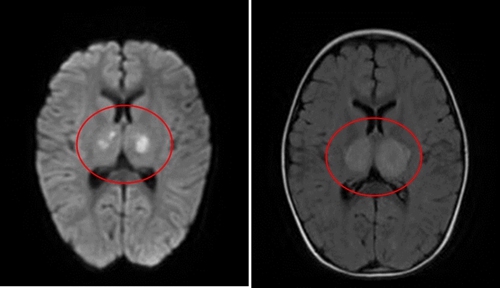

頭顱磁共振可顯示雙側丘腦有對稱性病變